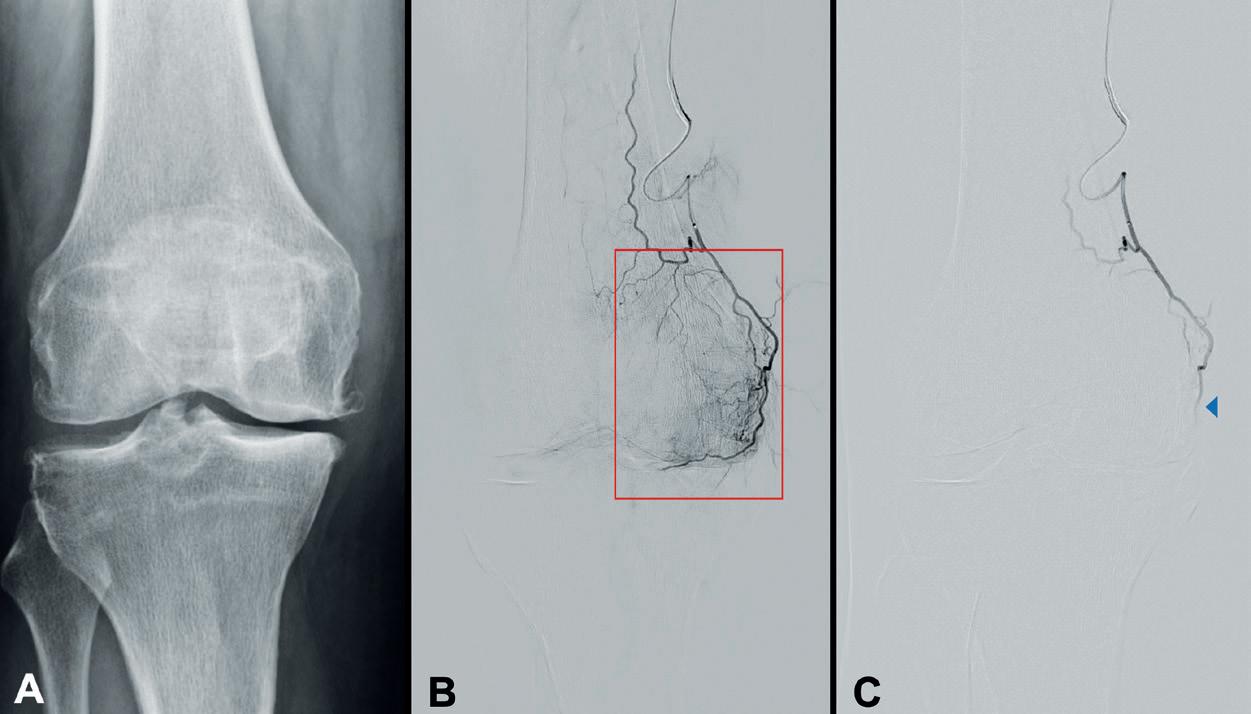

Data on peripheral intravascular lithotripsy (IVL) for the treatment of calcified lesions below the knee (BTK) in patients with peripheral arterial disease (PAD) have rapidly emerged in recent weeks. At the 2025 Vascular Interventional Advances (VIVA) conference (2–5 November, Las Vegas, USA), several studies including DISRUPT BTK II, FORWARD PAD, and POWER PAD II delivered positive reports, some contributing to the longest follow-up of patients treated with IVL to date. As industry races to produce data for the newest devices, clinicians speak to Interventional News on the outcomes that matter most as continued assessments determine how IVL fits in the armamentarium of calciummodifying technology.

Several late-breaking data presentations at VIVA 2025, Ehrin Armstrong (Swedish Medical Center, Denver, USA) shared 12-month results from the postmarket, prospective, multicentre DISRUPT BTK II trial, evaluating the Shockwave IVL system (J&J MedTech/Shockwave Medical) in 250 patients with 305 lesions across 38 sites globally.

In the study, 58.5% of patients presented with baseline wounds, 80% with chronic limb-threatening ischaemia (CLTI), 70% with diabetes mellitus, 30% with chronic total occlusions (CTOs) and 85% with moderate-to-severe calcium. The research team demonstrated a 94.8% freedom from major target limb amputation, with no amputations observed among non-CLTI patients. Freedom from clinically driven target lesion revascularisation (CD-TLR) was achieved in 84.5% of patients and Rutherford classification improvement was reported in 75.5% of patients at one-year follow-up.

Among those with CLTI at baseline, 8.1% of patients experienced an amputation. Significant symptomatic and

VascuQoL improvements were also documented, with a more than five-point increase from baseline (11.9±4 to 17.2±5, p<0.001) at one year.

Armstrong noted that the “DISRUPT BTK II study represents a complex, truly real-world patient and lesion cohort,” highlighting high rates of diabetes mellitus, severe target lesion calcification, dialysis-dependent renal failure and CLTI with wounds. He added that the trial has set a “new standard” by introducing IVL as a “frontline strategy” to modify calcification and restore vessel compliance.